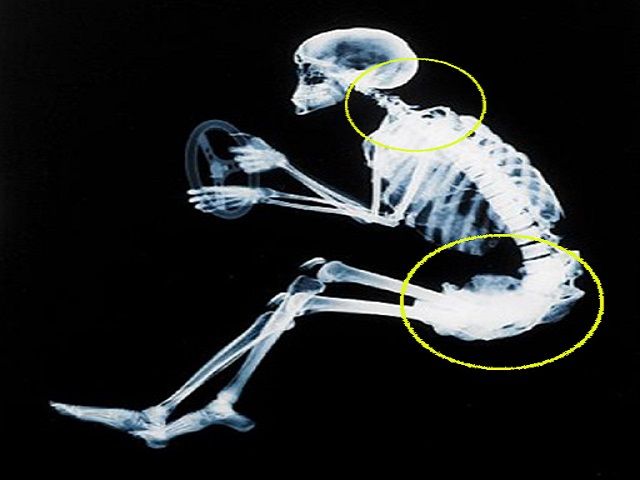

Buone notizie per chi rimane legato a

un lavoro sedentario: un mega-studio sulle cause del dolore alla schiena

esclude ogni associazione fra la prolungata posizione seduta e il dolore

lombare. Ricercatori dell’Istituto per l’Attività Fisica dell’università Deakin

di Melbourne hanno passato al vaglio 41 differenti revisioni sistematiche di

ricerche, per meglio comprendere quali movimenti o funzioni sono fattori per il

dolore alla schiena. I risultati, pubblicati sul Journal of Biomechanics, sono

basati su tre decenni di dati raccolti esaminando oltre un milione di soggetti

e offrono il quadro finora più accurato della relazione fra diverse attività e

il dolore alla schiena. “L’evidenza più

forte – scrive Daniel Belavy, docente di Esercizio e di Salute

Muscoloscheletrica, responsabile dello studio – è l’assenza di ogni associazione fra la posizione seduta, prolungata o

occupazionale, e il dolore lombare”.“Nonostante

subire rigidità muscolare se si resta

seduti a lungo, ma stare seduti di per sé non danneggia direttamente la struttura spinale, come invece avviene con

molti lavori pesanti”. Anche se stare seduti non sembra essere un problema